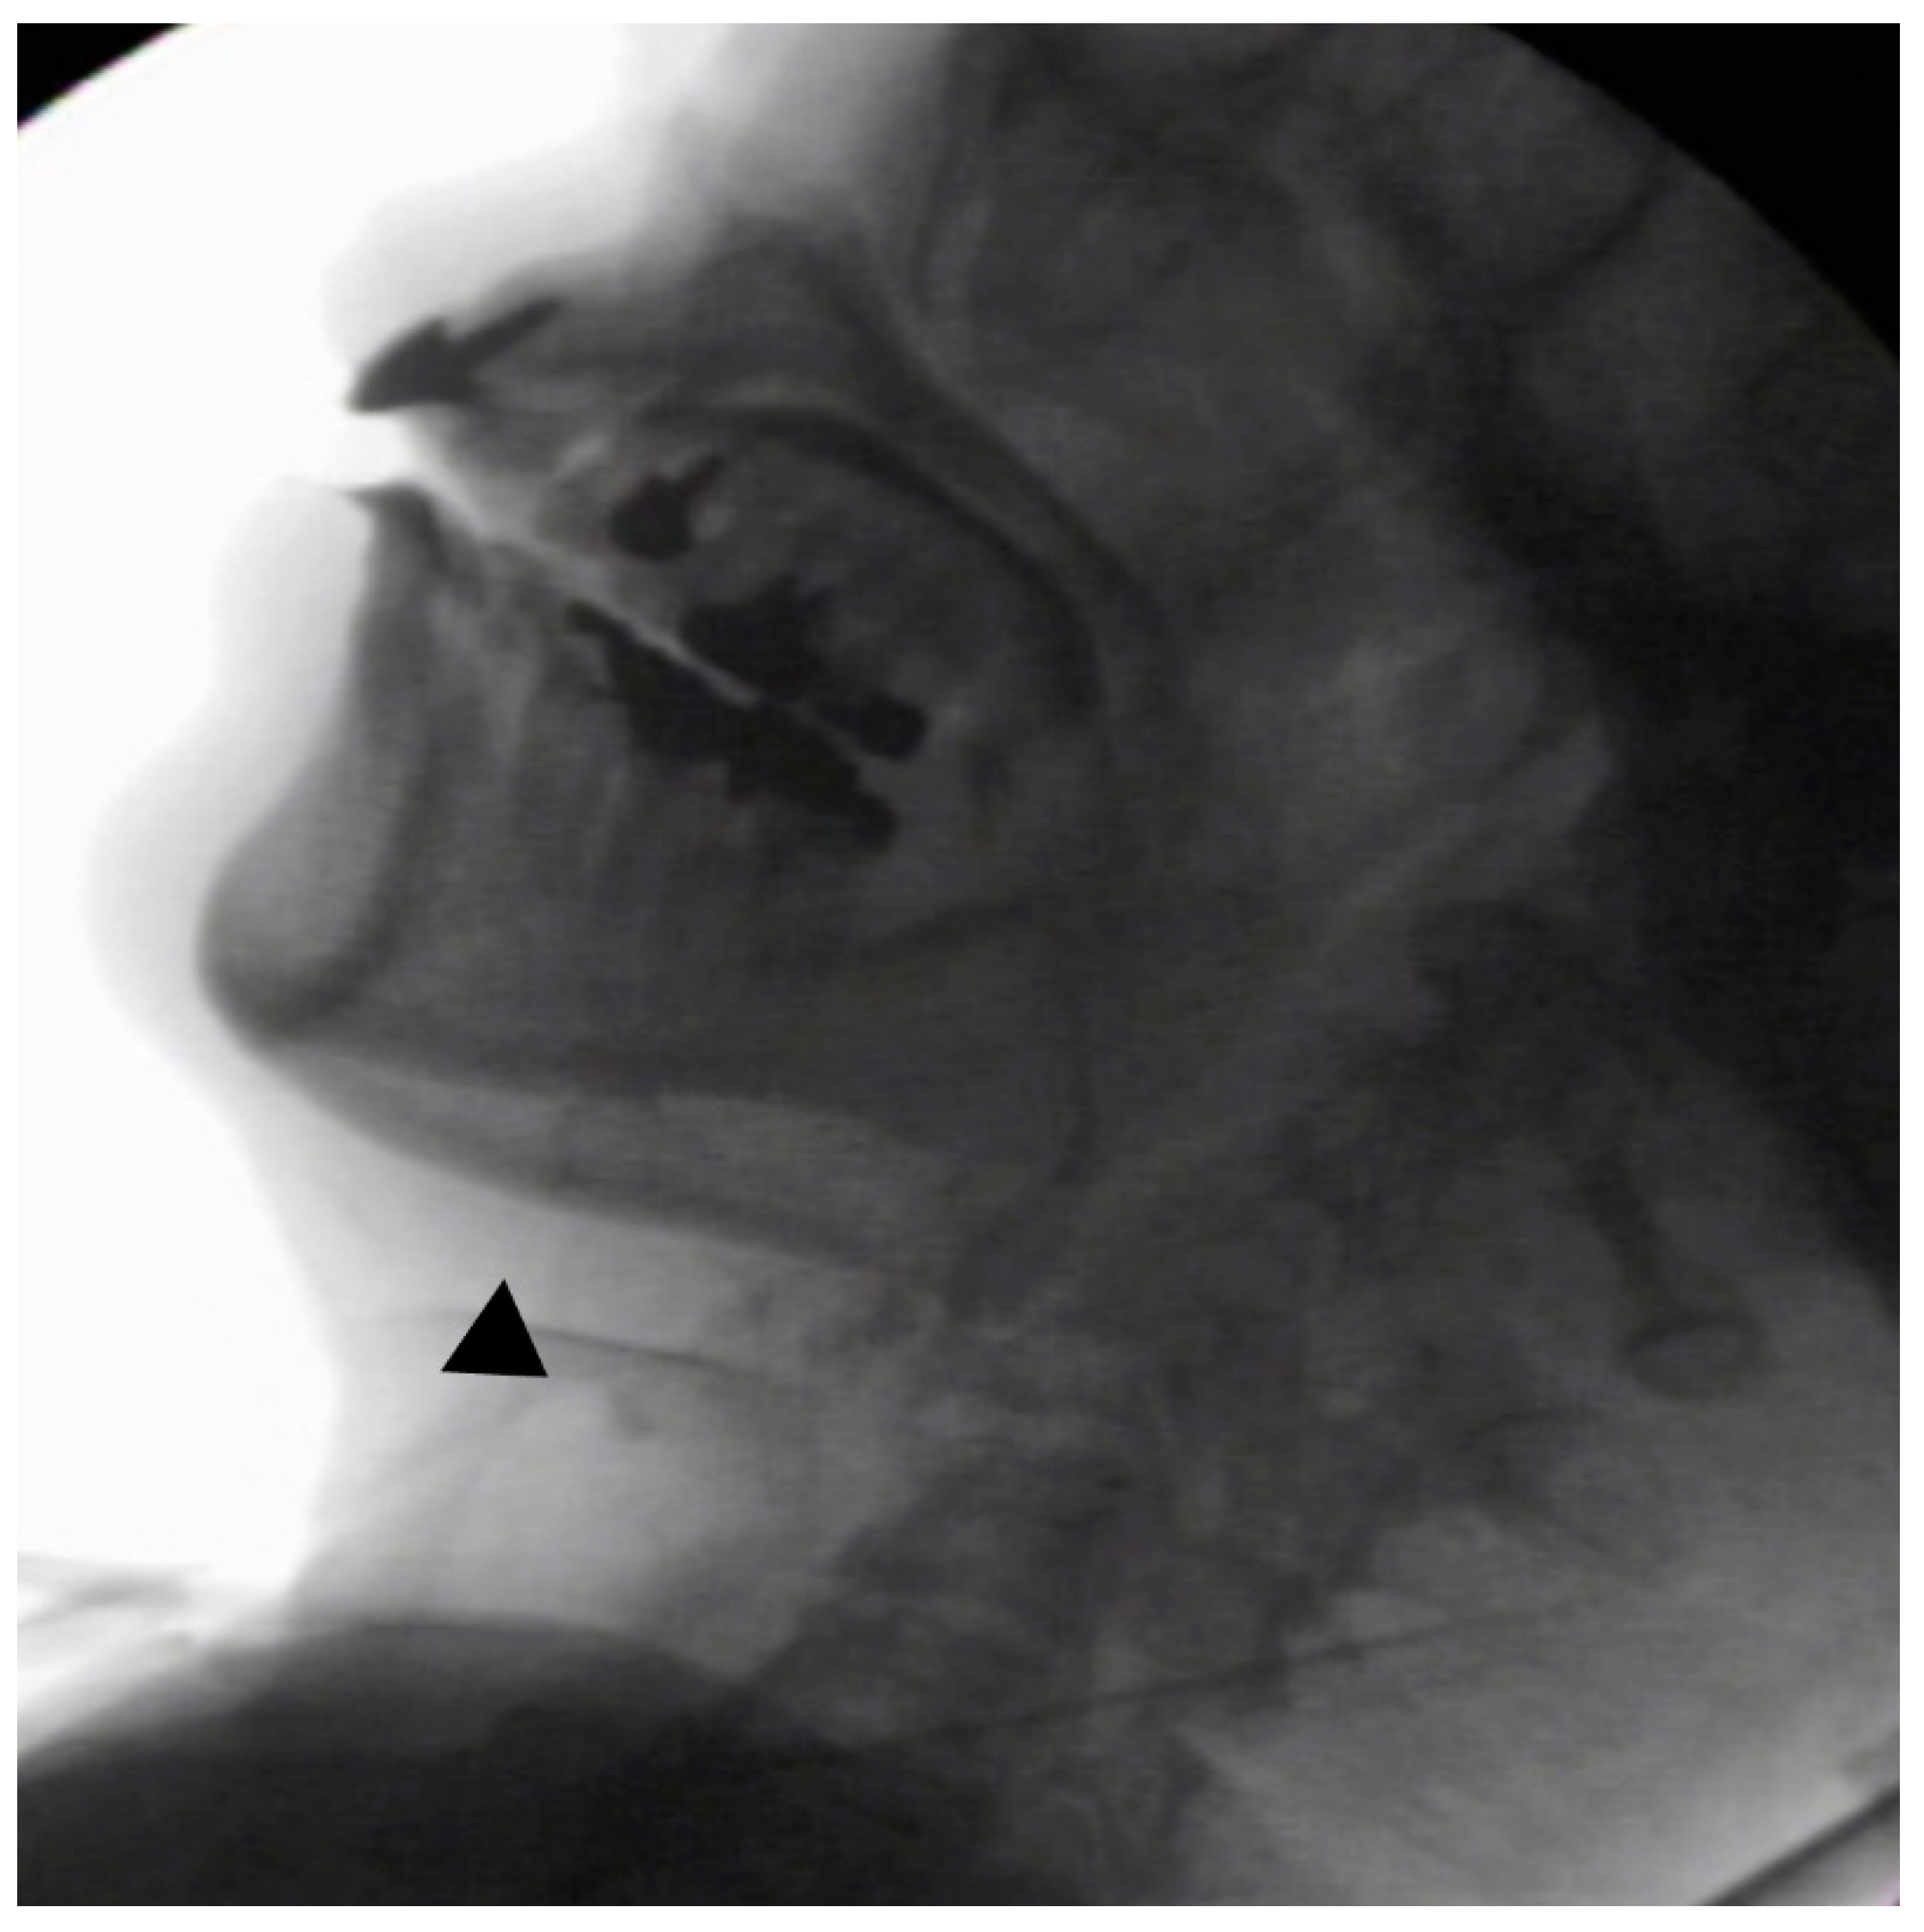

In the seated position, spoon-feeding was infeasible and bolus transport did not occur; furthermore, anterior–posterior tongue movement caused most of the food to dribble out of her mouth. After placing food on top of her tongue using a tube-fitted syringe, most still dribbled out of her mouth (Figure 1a); however, a proportion was transported into the pharynx (Figure 1b). Furthermore, after placing food at the back of her tongue with the patient reclined at 30°, a small amount still dribbled out of her mouth; however, the patient could swallow without aspiration (Figure 2). After increasing the amount placed in her mouth at one time to 7 mL, more food dribbled out of her mouth (Figure 3); additionally, there was a decreased amount transported to the pharynx. When 5 mL of a moderately thick paste was placed in her mouth, none of it dribbled out; however, slight silent aspiration was present (Figure 4). There were no particular issues observed due to peristalsis from the upper esophagus to the stomach.

Figure 4.

The patient was reclined at 30° for the administration of 5 mL of a moderately thick paste. There was delayed triggering of the swallowing reflex; moreover, silent aspiration occurred (▲).